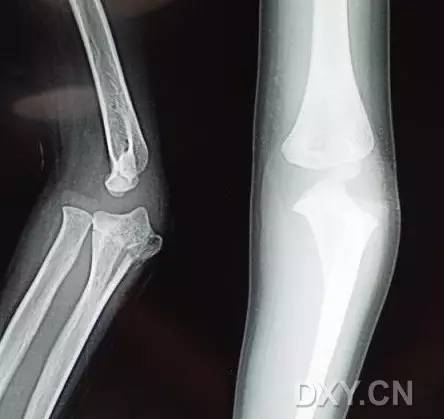

10. Galeazzi 骨折(盖氏骨折)

桡骨干下 1/3 骨折合并尺骨小头脱位。

盖氏骨折正侧位(来源:Orthobullets)